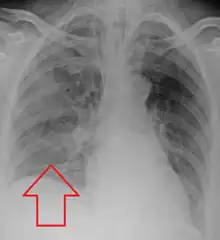

Aspiration pneumonia is typically diagnosed by a combination of clinical circumstances (people with risk factors for aspiration) and radiologic findings (an infiltrate in the proper location).[1] A chest x-ray is typically performed in cases where any pneumonia is suspected, including aspiration pneumonia.[18] Findings on chest x-ray supportive of aspiration pneumonia include localized consolidation depending on the patient's position when the aspiration occurred.[18] For example, people that are supine when they aspirate often develop consolidation in the right lower lobe of the lung.[18] Sputum cultures are not used for diagnosing aspiration pneumonia because of the high risk of contamination.[19] Clinical symptoms may also increase suspicion of aspiration pneumonia, including new difficulty breathing and fever after an aspiration event.[6] Likewise, physical exam findings such as altered breath sounds heard in the affected lung fields may also be suggestive of aspiration pneumonia.[6] Some cases of aspiration pneumonia are caused by aspiration of food particles or other particulate substances like pill fragments; these can be diagnosed by pathologists on lung biopsy specimens.[20]